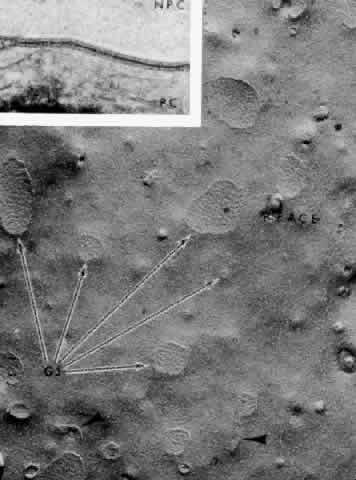

Fig. 21. A zonula occludens “tight” junctional area (TJ) between nonpigmented

epithelial cells in Macaca mulatta as seen by the freeze-fracture

technique. It shows a network of anastomosing grooves (arrows) on

the outer plasmalemmal leaflet, giving a quilted effect. A few fragments

of the complementary strands from the inner leaflet (P-face) are

still adherent. (X 60,500; Courtesy of Dr. Guiseppina Raviola) Fig. 21. A zonula occludens “tight” junctional area (TJ) between nonpigmented

epithelial cells in Macaca mulatta as seen by the freeze-fracture

technique. It shows a network of anastomosing grooves (arrows) on

the outer plasmalemmal leaflet, giving a quilted effect. A few fragments

of the complementary strands from the inner leaflet (P-face) are

still adherent. (X 60,500; Courtesy of Dr. Guiseppina Raviola)

Gap junctions occur in “extraordinary numbers” in the ciliary

epithelium and may be found even among the strands of zonula occludens.23 At gap junctions, the surface membranes of the two cells run a very straight

course. They are separated only by a 2- to 3-nm cleft, which becomes

filled with reaction product in tracer experiments (Fig. 22, Inset). In freeze-fractured specimens, gap junctions are easily recognized

as rounded patches of 8- to 9-nm particles arranged in crystalline-like

array on the inner plasmalemmal leaflet (see Fig. 22), matched by pits on the outer surface. The plethora of gap junctions

in the ciliary epithelium indicates that the cells are closely coupled

for electrical and metabolic cooperative work across these sites of low

ionic resistance.  Fig. 22. Inset. A gap junction between pigmented and nonpigmented epithelial cells (NPC) in

Macaca mulatta. The tracer horseradish peroxidase, injected

in vivo, has filled the small gap between the cell plasma membranes. Main

figure. Gap junctions (GJ) at apex of nonpigmented epithelial cells

are rounded aggregates of 8- to 9-nm particles (arrows) on the inner

leaflet (P-face) of the plasmalemmal membrane. Zonula occludens-like

strands are frequently seen at the periphery (arrowheads). (Freeze-fracture, X 34,000; Inset, X 168,000; Courtesy of Dr. Guiseppina

Raviola) Fig. 22. Inset. A gap junction between pigmented and nonpigmented epithelial cells (NPC) in

Macaca mulatta. The tracer horseradish peroxidase, injected

in vivo, has filled the small gap between the cell plasma membranes. Main

figure. Gap junctions (GJ) at apex of nonpigmented epithelial cells

are rounded aggregates of 8- to 9-nm particles (arrows) on the inner

leaflet (P-face) of the plasmalemmal membrane. Zonula occludens-like

strands are frequently seen at the periphery (arrowheads). (Freeze-fracture, X 34,000; Inset, X 168,000; Courtesy of Dr. Guiseppina

Raviola)